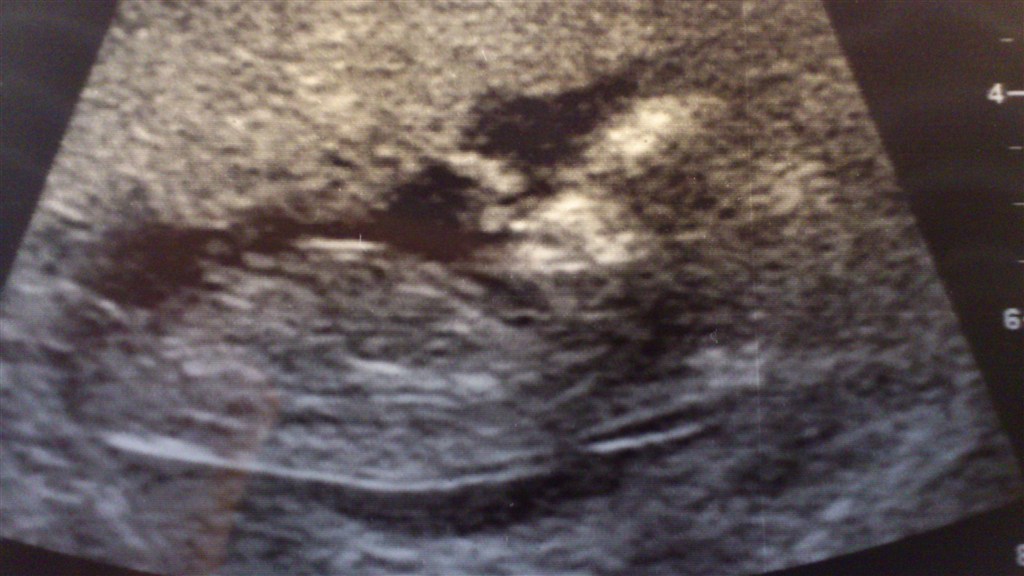

Så kom dagen endelig! Det var en fantastisk skanning. Var så nervøs og da Blyp så kom på skærmen og vi kunne se det lille hjerte banke var alt bare godt igen. Den hopper og sutter på fingre der inde

Fik et tal på 1:20.307 og termin stadig 11. Maj.

Valgte at ligge billedet ind hvor Blyp sutter på fingre. Synes det er enormt hyggeligt at tænke på.